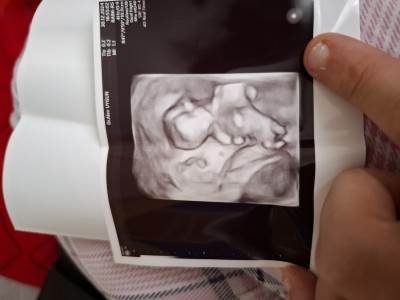

Sizce cinsiyet nedır kızlar

13+4

Hislerime göre kesin kız ama hislerime göre öğrenince yaz :)

Kız canım rabbim gönlüne göre versin

Bacak arası düz çıkıntı yok canim